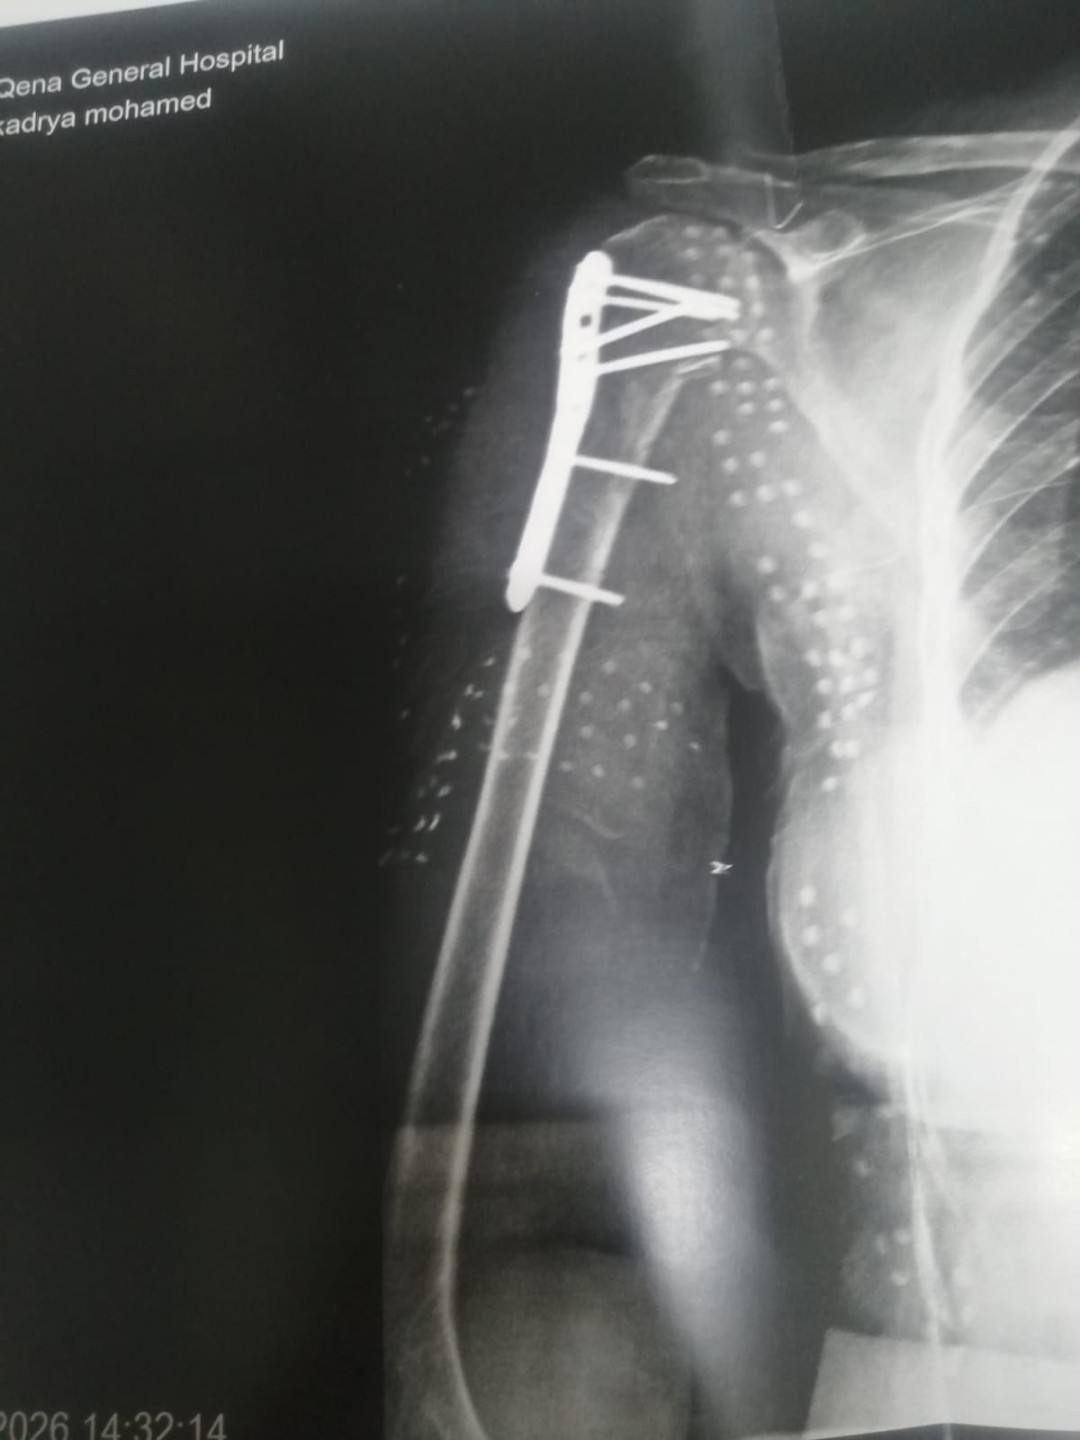

وفي سياق متصل نجح فريق جراحة العظام في إجراء عملية جراحية دقيقة لمريضة تبلغ من العمر 69 عامًا كانت تعاني من كسر أعلى عظمة العضد حيث تم تصليح الكسر وتركيب شريحة ومسامير تيتانيوم وتكللت العملية بالنجاح واستقرت حالة المريضة

وأجرى العملية فريق طبي ضم الدكتور محمد رمضان، والدكتور حسن محمود، والدكتور عمر محفوظ، تحت إشراف التخدير للدكتور حسن مبارك، وبمشاركة فريق تمريض العمليات